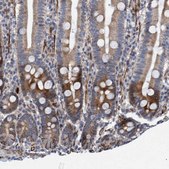

Application:

IHC

immunohistochemistry: 1:20- 1:50

All Prestige Antibodies Powered by Atlas Antibodies are developed and validated by the Human Protein Atlas (HPA) project and as a result, are supported by the most extensive characterization in the industry.

The Human Protein Atlas project can be subdivided into three efforts: Human Tissue Atlas, Cancer Atlas, and Human Cell Atlas. The antibodies that have been generated in support of the Tissue and Cancer Atlas projects have been tested by immunohistochemistry against hundreds of normal and disease tissues and through the recent efforts of the Human Cell Atlas project, many have been characterized by immunofluorescence to map the human proteome not only at the tissue level but now at the subcellular level. These images and the collection of this vast data set can be viewed on the Human Protein Atlas (HPA) site by clicking on the Image Gallery link. We also provide Prestige Antibodies® protocols and other useful information.

• IHC tissue array of 44 normal human tissues and 20 of the most common cancer type tissues.